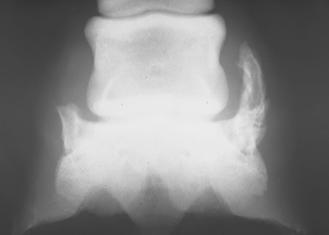

Čiurnos sąnario rentgenogramose tiek dešinėje, tiek kairėje pusėje OCD pasireiškė tokiu pat dažnumu – po aštuonis atvejus. Osteochondrinių atplaišų dydis sąnariuose svyravo nuo žirnio iki pupos dydžio.

Dažniausiai pažeidimai buvo lokalizuoti dorsaliai čiurnos sąnario, plantariniame paviršiuje, rečiau – palmariniame paviršiuje. Dviem atvejais buvo nustatyti įtrūkimai sąnario sagitalinėje kameroje.

25 pav. Kairėje – sveikas čiurnos sąnarys, dešinėje – sąnarys, pažeistas OCD.